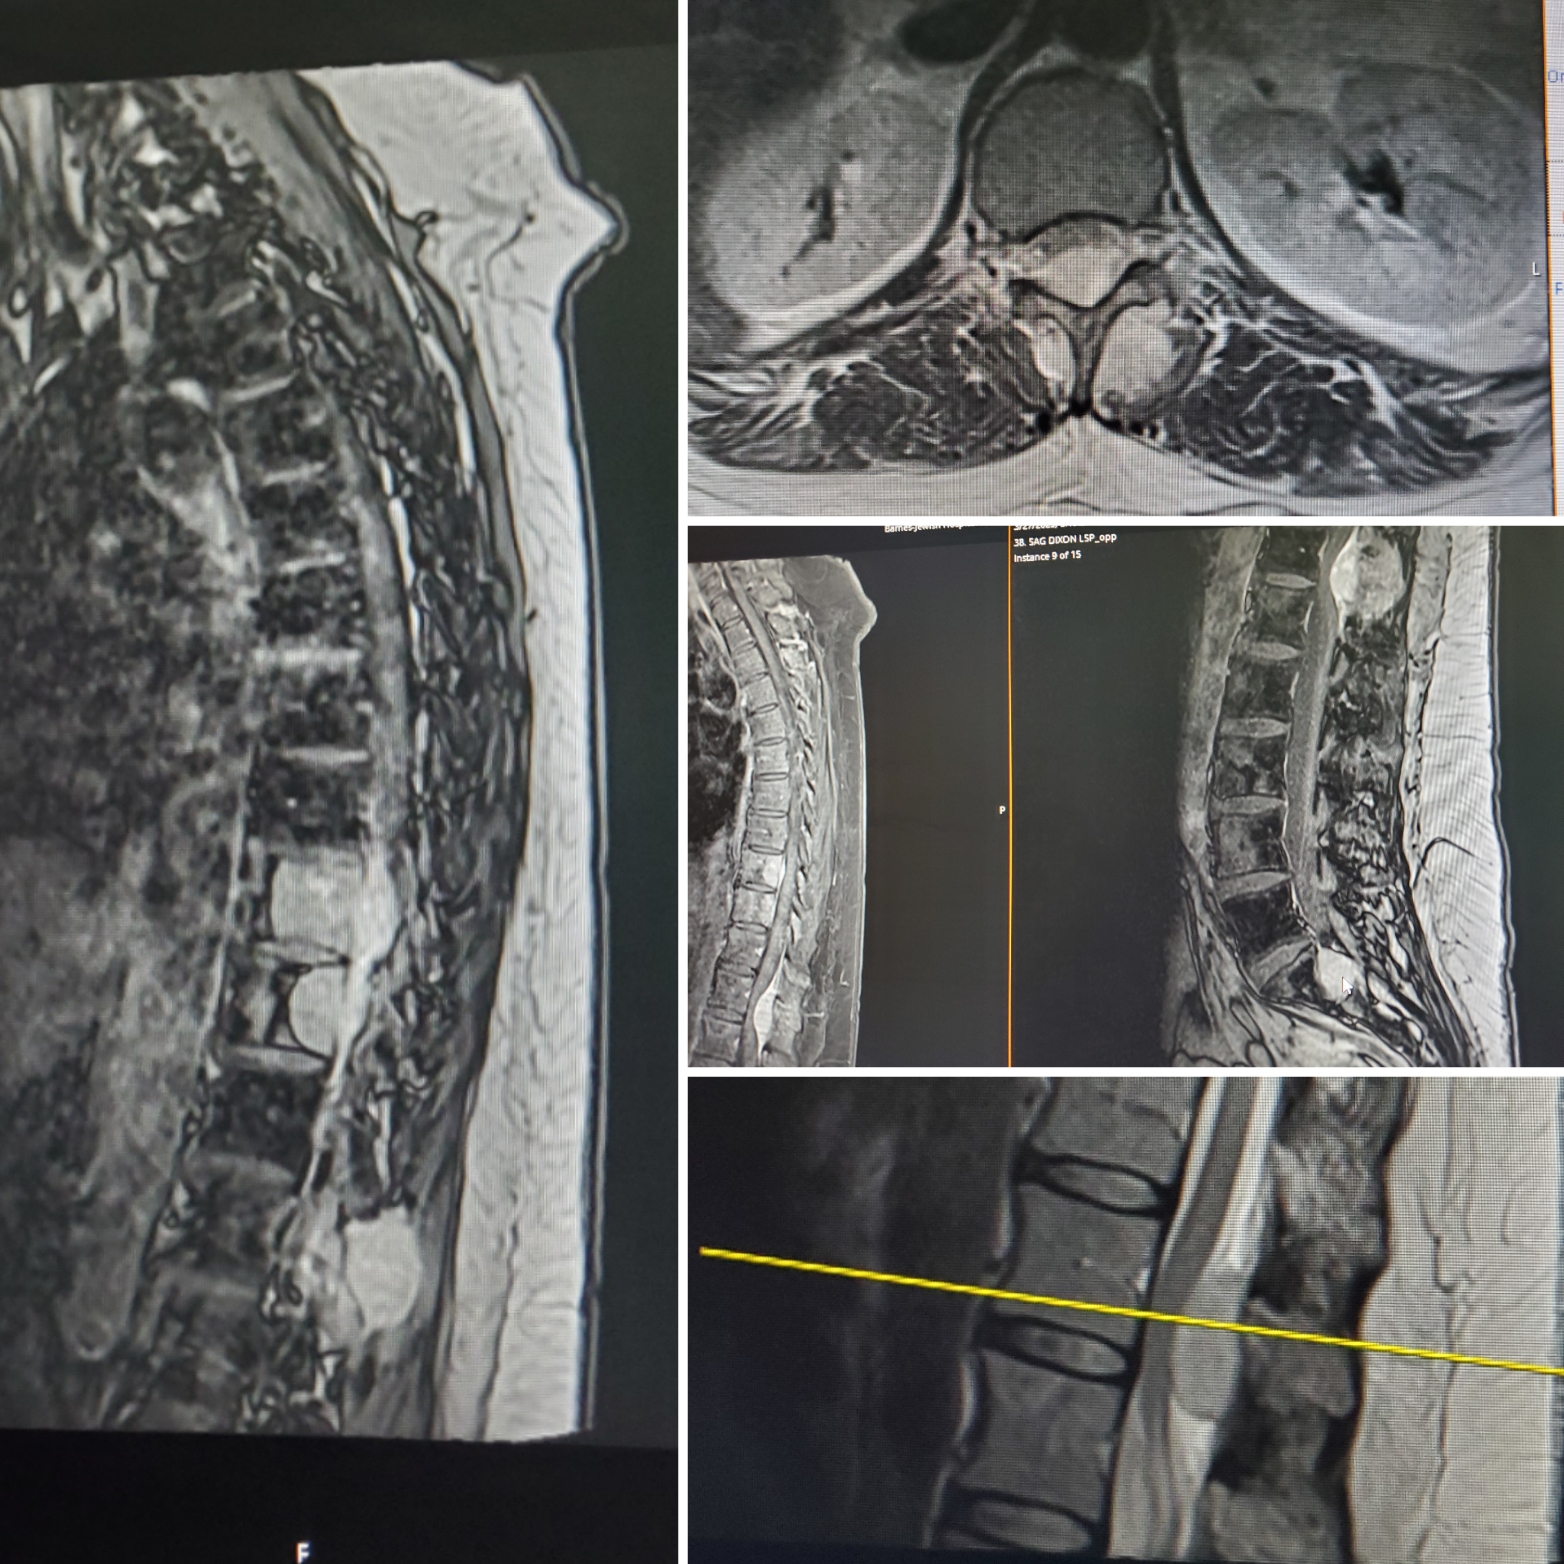

Emily has been diagnosed with Stage 4 Advanced Metastatic Neuroendocrine Cancer. It has spread to many areas of the body, including several tumors in the liver, multiple tumors on and around the spine and spinal cord. It is in the left arm humerus bone, several areas in the right femur bone, bilaterally across the entire pelvis in the bone, in several rib bones, and several vertebrae.

The most serious of the tumors is causing spinal cord compression and nerve damage and could lead to paralysis. So it needs to be dealt with first and quickly. Spine surgery will be done on Wednesday, the 2nd of April, to try and remove this tumor and release the pressure on the spinal cord.